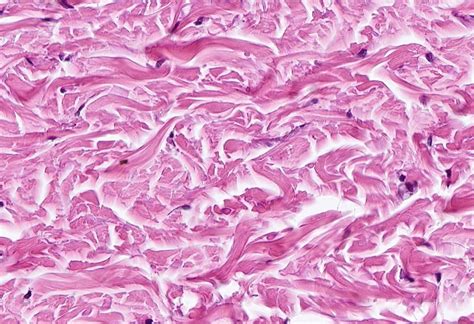

Dense Irregular Ct Scan Image

• dense irregular connective tissue

• dense irregular ct found where

• dense irregular function and location

• dense irregular ct location